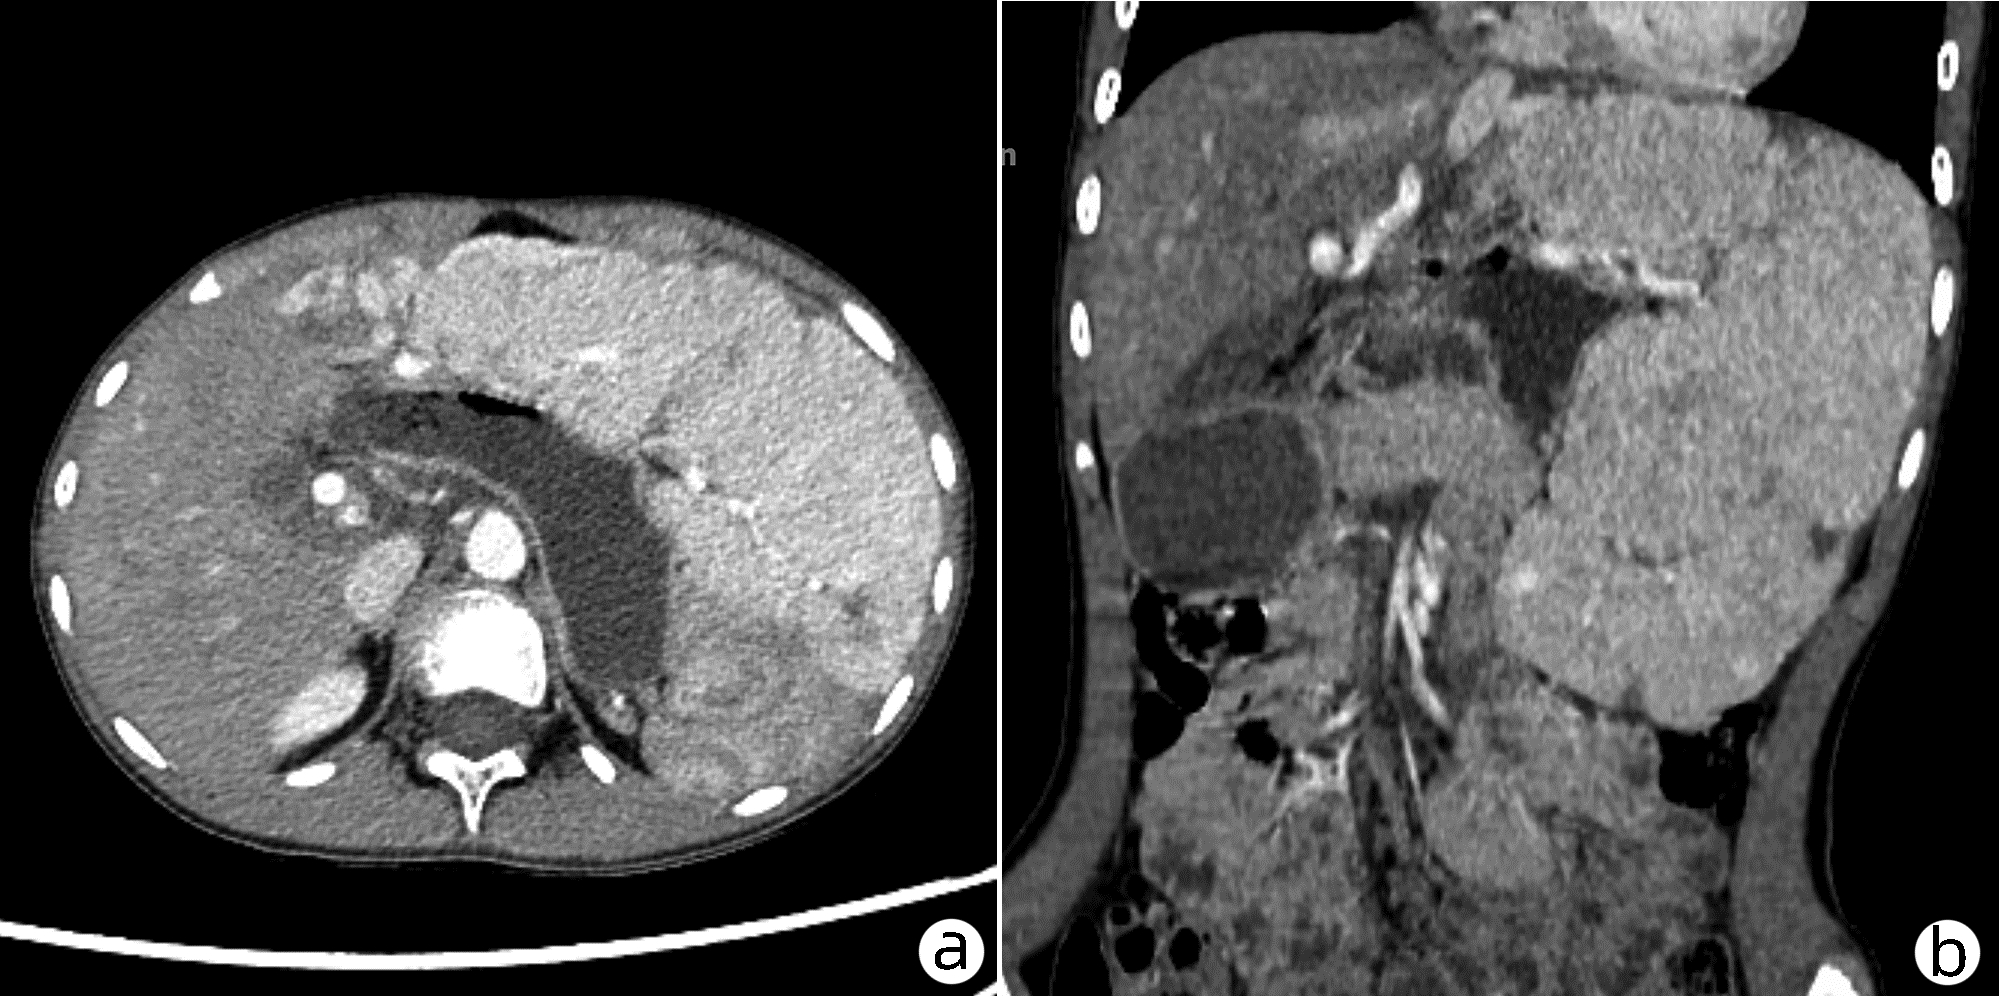

Carcinosarcoma of the liver: A case report

Liang CHEN, Jincai WU, Jiacheng CHEN, Xiangxiang LUO, Rong TANG, Hande QIN, Kailun ZHOU

2022, 38(6): 1373-1374. DOI: 10.3969/j.issn.1001-5256.2022.06.030

Abstract(1091) HTML (198) PDF (3285KB)(62)

Abstract: